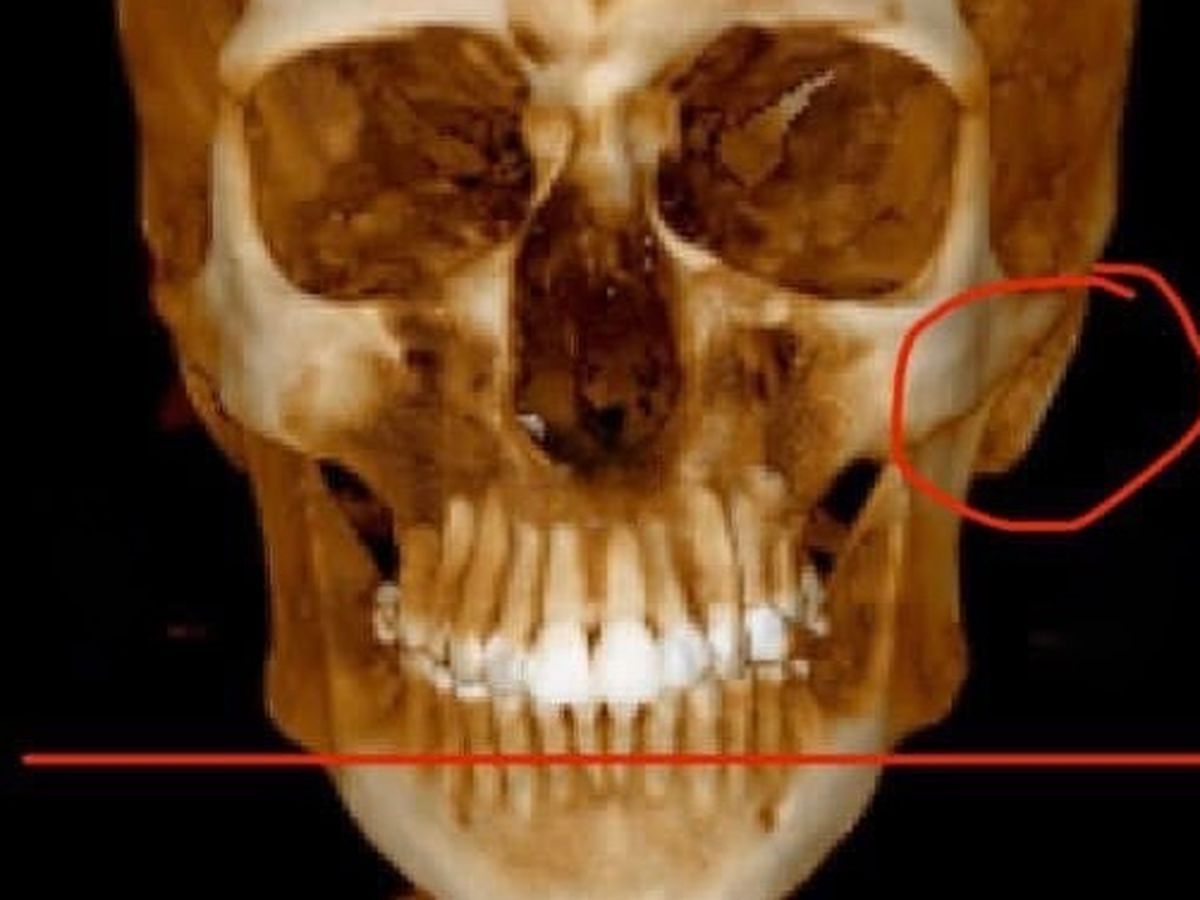

I was diagnosed with TMJ this year, which is a whole new adventure that I’m struggling to begin since no oral surgeon wants to see someone with Ehlers-Danlos Syndrome since it is a connective tissue disorder. TMJ is very common with EDS. My only choice right now is to travel down to NYC again to see an oral surgeon knowledgeable in EDS, but that will all be out of pocket expenses.

My cervical spine curves the opposite way (kyphosis).